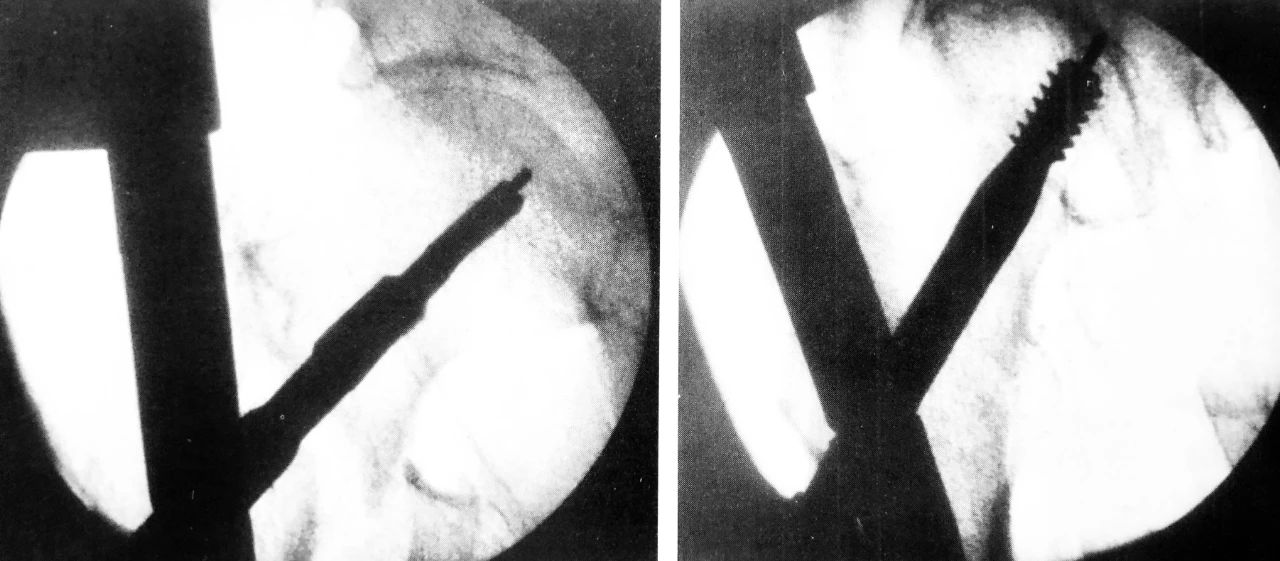

肱骨逆行髓内钉,左图为入钉口置备,右图为穿入多根弹性髓内钉